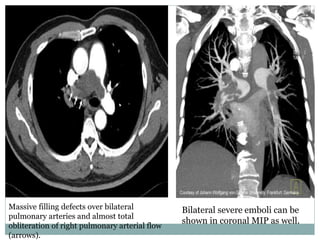

Massive filling defects over bilateral

pulmonary arteries and almost total

obliteration of right pulmonary arterial flow

(arrows).

Bilateral severe emboli can be

shown in coronal MIP as well.

Massive filling defectsover bilateral pulmonary arteries and almost total obliteration of right pulmonary arterial flow (arrows). Bilateral severe emboli can be shown in coronal MIP as well.